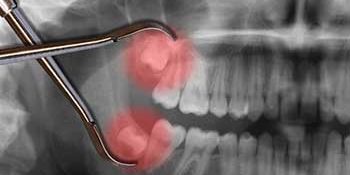

It all depends on the angle of the tooth, and if roots are close to a nerve. If the tooth must come out at a dodgy angle, it can be more difficult to extract, requiring bone removal and stiches. There is also a nerve that runs near the roots of wisdom teeth. If this nerve is close to the roots (this can be assessed by taking a simple x-ray), there is a chance the nerve can be damaged. That can lead to temporary or permanent numbness of that side of the mouth. This is rare, but it is always good to check where the nerve is, before taking wisdom teeth out. We use a CT scanner to take a 3D image of the area, so we can precisely locate the nerve. There are only a handful of dentists that have this technology.